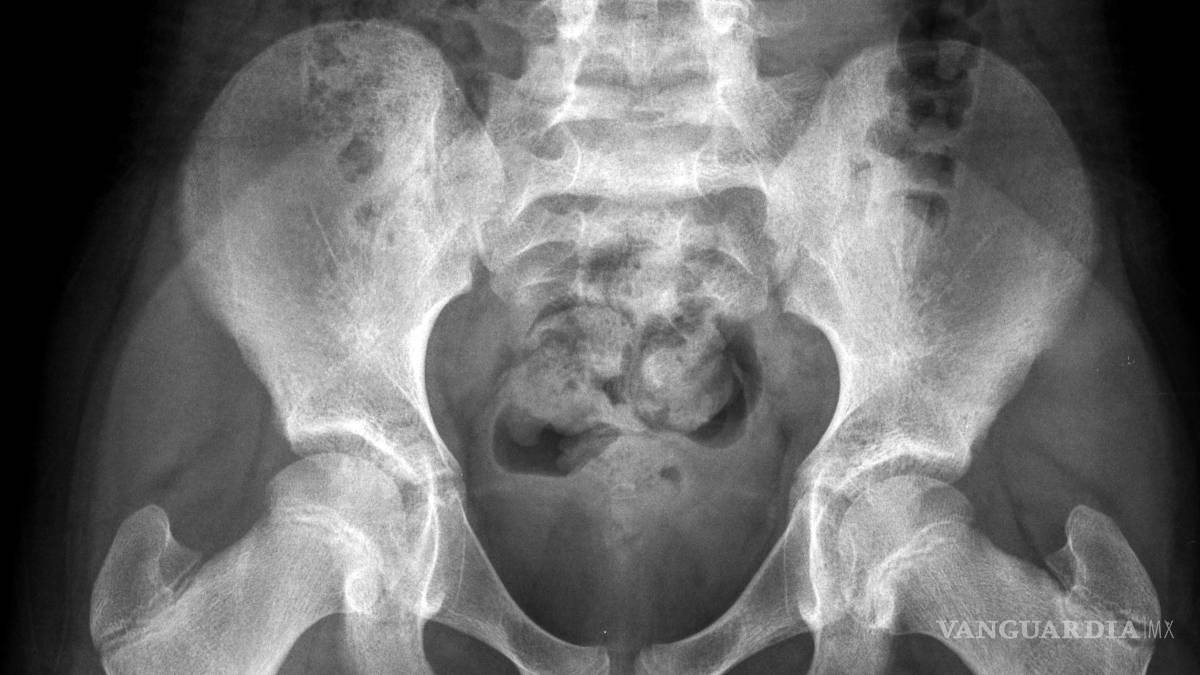

El principal problema es que la pelvis de las niñas es demasiado estrecha como para que pueda pasar incluso un feto pequeño, señaló Ashok Dyalchand, un médico que ha trabajado con adolescentes embarazadas en comunidades de bajos ingresos en la India durante más de 40 años.

“La labor de parto que experimentan es prolongada y obstruida, el feto aplasta la vejiga y la uretra” y a veces provoca la enfermedad pélvica inflamatoria y la ruptura de los tejidos que hay entre la vagina y la vejiga y el recto, señaló Dyalchand, quien dirige el Instituto de Gestión Sanitaria Pachod, que es una organización de salud pública que atiende a las comunidades marginadas en la zona central de la India.

“Las chicas pasan por un trabajo de parto de tres, cuatro, cinco días y después de ese tiempo, el bebé casi siempre está muerto. Y el bebé sale cuando se hunde la cabeza”, explicó Syed, quien es uno de los especialistas más prominentes de Asia del Sur en la reparación de la fístula obstétrica, un resultado habitual del parto obstruido en las niñas embarazadas.

En casi todos estos casos, la niña desarrolla una fístula vesicovaginal, que es un agujero entre la pared de la vejiga y la vagina. En una cuarta parte de los casos, el trabajo de parto prolongado también origina una fístula del recto, por lo que la chica deja salir orina y excremento de manera constante.